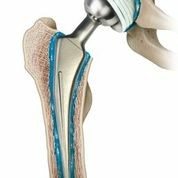

Основным эффективным и адекватным методом терапии является эндопротезирование ТБС — замена разрушенного суставного соединения на имплантат.

Эндопротезирование — сложный вид ортопедической хирургии, требующий от специалиста высокой квалификации, современных технологий и оборудования.

Протез первого типа рекомендован людям престарелого возраста, поскольку у них наблюдается значительное ослабление костной ткани, выраженные признаки остеопороза. Второй тип ставится молодым людям: например, спортсменам, получившим травмирование ТБС. Данный имплантат устанавливают пациентам до 40 лет, отзывы — положительные.